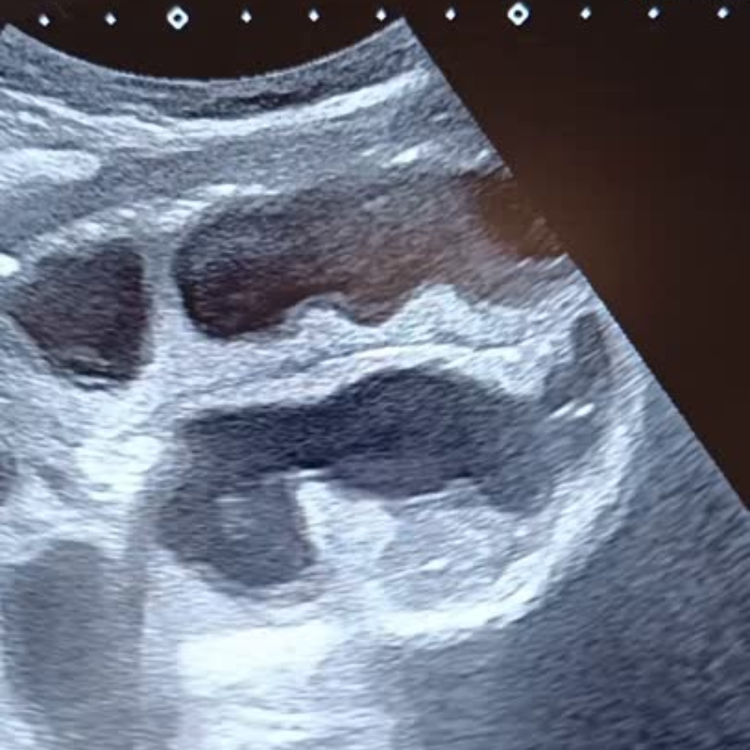

Occlusion : identifier le blocage en urgence.